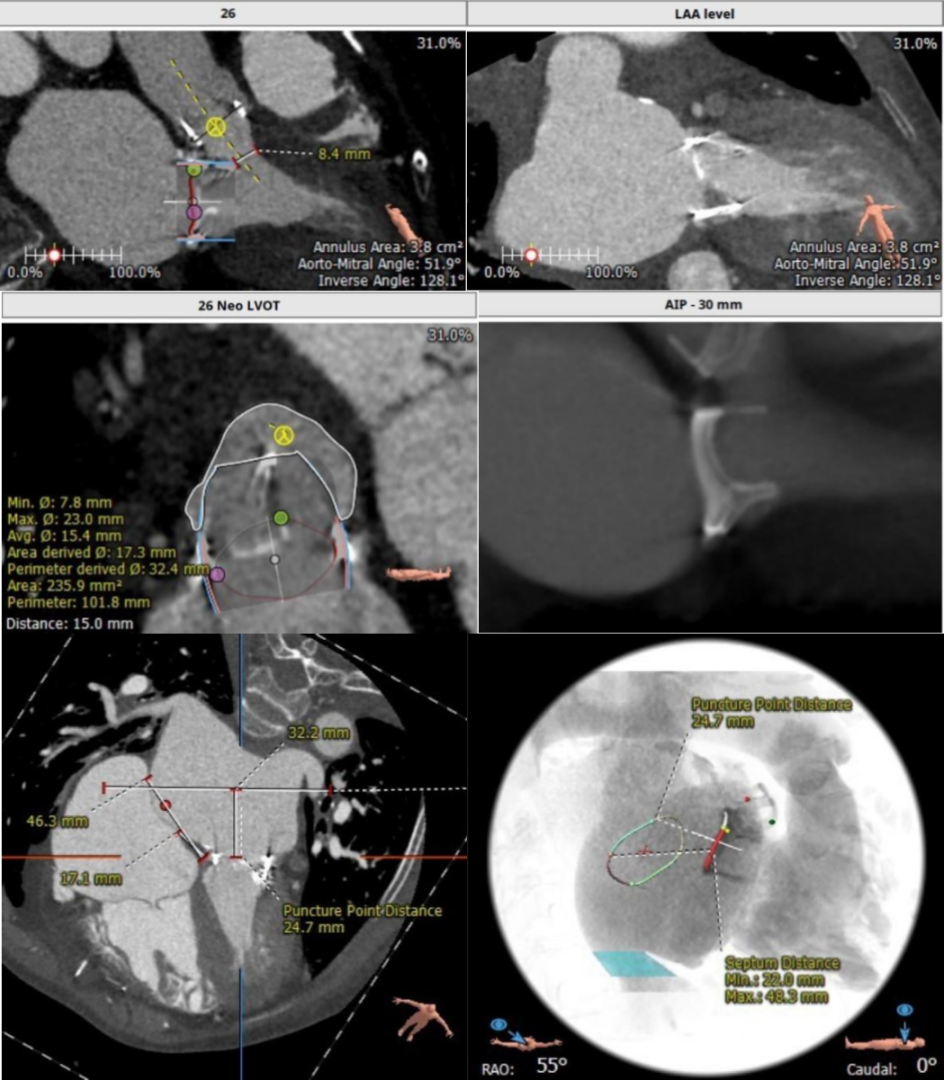

经过充分的术前食道超声及心脏CTA的评估,团队一致选择目前国际上瓣中瓣(Valve in Valve)技术使用最多最成熟的器械——Edwards SAPIEN3瓣膜。与林阿姨及其家属充分沟通后,在经验丰富的王焱院长的指导下,珠海市人民医院结构性心脏病团队决定为林阿姨同期进行主动脉瓣及二尖瓣的双瓣膜置换,采用的方案是先经股动脉途径为其行主动脉瓣的瓣中瓣植入(VinV TAVR),然后经股静脉途径,穿刺房间隔后,行二尖瓣的瓣中瓣植入(VinV TMVR),视情况对房间隔穿刺后的缺损进行封堵。

二尖瓣瓣中瓣CT评估